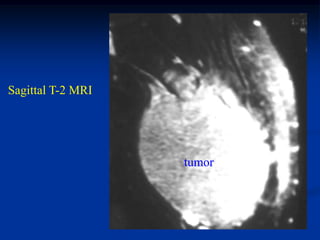

Sagittal T-2 MRI

tumor